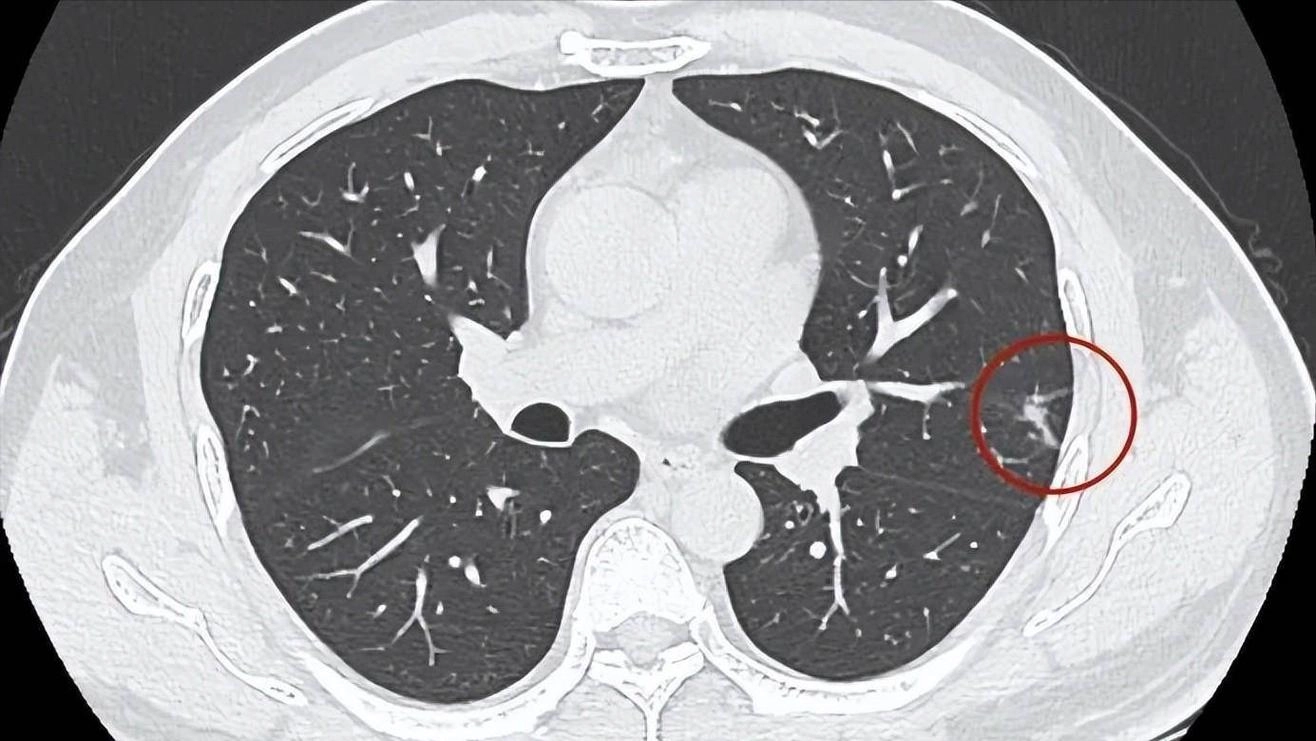

医生还发现一个细节:很多肺癌患者在确诊前1年,肺部CT其实已经出现微小结节,只是被当成“良性结节”观察处理了。

如果当时能进一步做增强CT、PET-CT,甚至穿刺活检,或许可以提前半年甚至一年发现。

这里必须强调一个常被误解的点:良性结节≠安全无忧。临床上,直径小于8毫米的结节不代表没风险,尤其是边缘毛糙、密度不均、伴随血管征象的“磨玻璃结节”,极有可能是早期腺癌的表现,必须密切随访。

临床上曾有一位五十多岁的中年人,非吸烟者,体检时查出一个6毫米的右肺结节,医生建议三个月复查,他嫌麻烦没管。

半年后复查,结节长到了1.5厘米,且出现血供增强,穿刺活检证实为早期腺癌。幸运的是,手术切除后病灶未扩散,算是捡回了一条命。